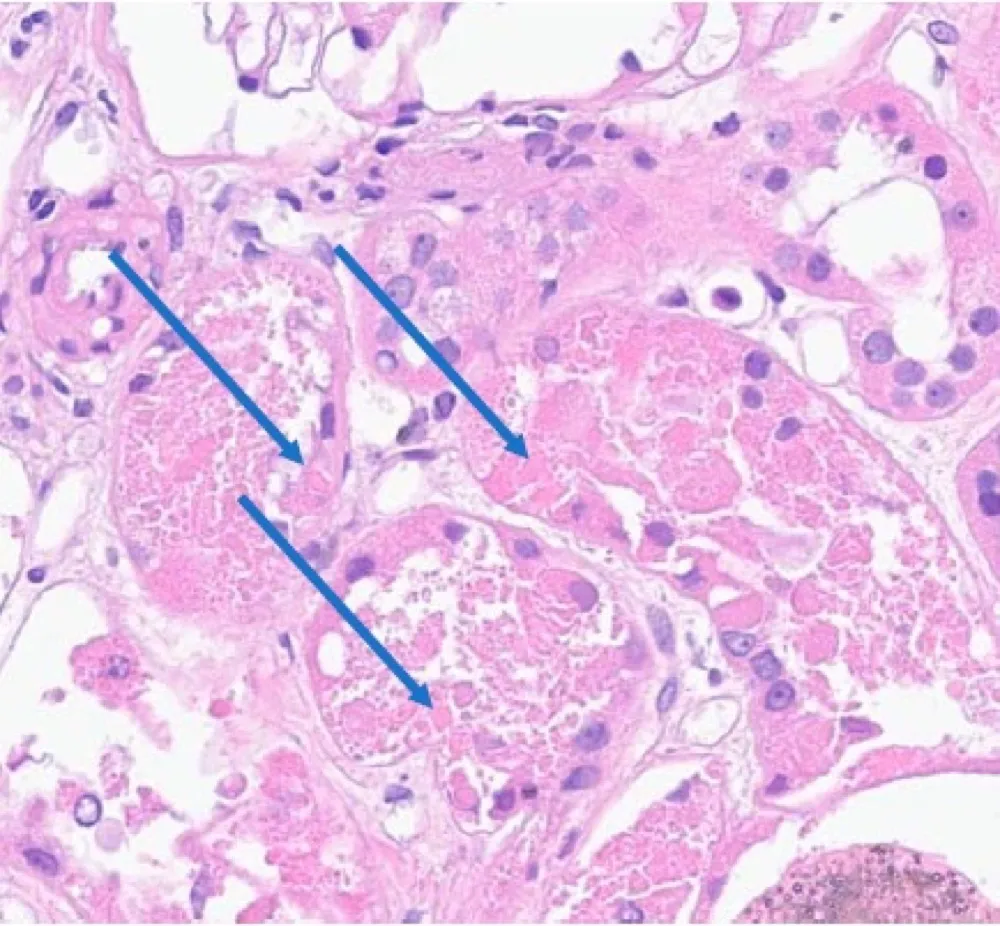

Paciente dislipidêmica, 47 anos, tomando suplemento "natural" para colesterol. Nenhuma queixa renal — até a creatinina chegar em 4.26. O agente não era uma droga controlada. Era arroz vermelho fermentado. E o rim foi o alvo.